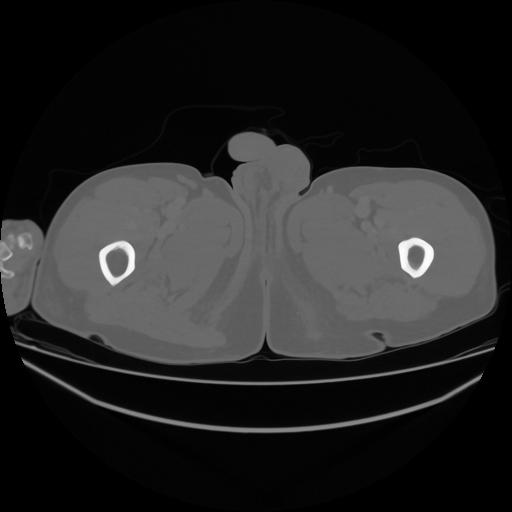

5 CUERPO,CE,Vol,1.0,CUERPO,,